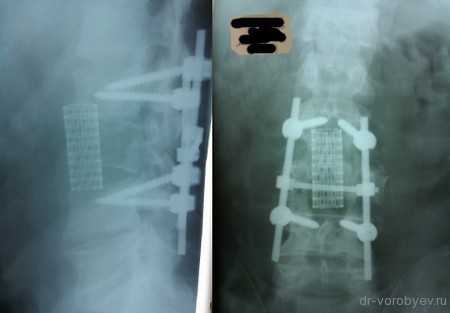

Перелом тела первого поясничного позвонка

Вид операционной раны. На место удаленного тела позвонка, после декомпрессии установлен протез тела позвонка Obelisk, Ulrich, Германия

Протез дополнительно фиксирован тораколюмбальной пластиной.

Рентгенологический контроль после операции.

Передний корпородез с использованием телескопического протеза тела позвонка Synex, фирма Synthes, США.

Протез помещен между телами смежных позвонков.

Интраоперационный рентгенологический контроль.